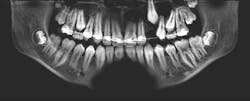

A 14-year-old female presented to her general dentist complaining of pain in the right posterior mandible and mobility of tooth no. 31. Her medical history was otherwise unremarkable. A panoramic radiograph revealed a large, multilocular radiolucent lesion within the entire ramus and posterior body of the right mandible. Tooth no. 32 was within the lesion. Cortical expansion in the area of the lesion was notable. All adjacent teeth were vital. A panoramic radiograph taken at the completion of orthodontic treatment 18 months previously showed no evidence of the lesion.

The keratocystic odontogenic tumor of the right posterior mandible was treated in the classical fashion for this entity by aggressive enucleation and curettage. Preoperatively, a 3D stereolithographic model of the mandible was obtained (figures 1-5), with the extent of the lesion defined, primarily to facilitate ease of adaptation should it be determined intraoperatively that a reconstruction plate would be required to reinforce the compromised mandible.

The lesion was removed via an intraoral approach and curetted from the cavity with the cyst intact. A margin of the cavity was removed using a rotary bur, and the cavity was treated with Carnoy’s solution following removal. Tooth no. 31 was noted to be intimately associated with the cyst and was removed. In four months since the surgery, repeat CBCT has demonstrated excellent bone formation within the cavity and no evidence of recurrence (figure 6).